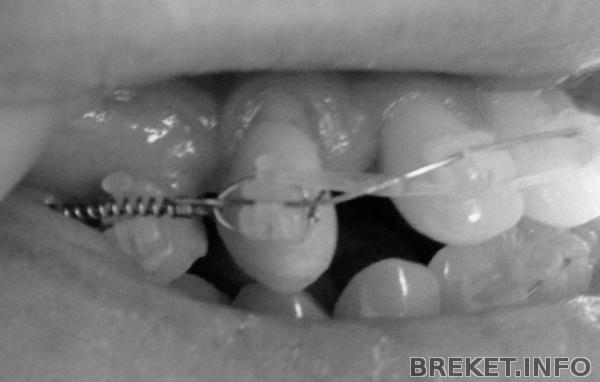

Мне кажется, справа я похожа на Бабу Ягу, я даже не знаю как менее страшно выглядит фото моего проблемного места - в цвете или ч/б, так что прилагаю оба. Ещё и десна не хочет спускаться, и эта фигня темная на шейке зуба, я думала камень и надо счищать, ортофея сказала так и должно быть и ничего делать не надо... ![]()

Эшли почти))) пружина тянет в сторону 6ки, а чейн убирает наклон 2-1-1, но, действительно, за счет этого самого клыка... То есть, по сути, он стоит на месте, а пружина посредством чейна тянет 2-1-1, потому что когда установили чейн, клык перестал двигаться в сторону пятерки.... как-то так))) Но пошатывается он неслабо, бедный)